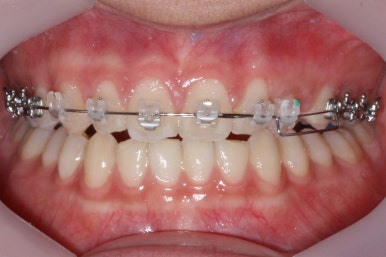

치료가 거의 종료가 되었습니다.

치아의 각도 등 미세한 조절을 좀 더 해주면 마무리를 할 수 있겠습니다.

마무리 때의 사진입니다.

윗니만 부분교정하였지만 교합에도 이상 없이 매복되었던 송곳니는 매우 잘 위치를 잡았습니다.

송곳니 부위는 다시 틀어지지 않게 하기 위해 유지철사를 붙여주었습니다.

총 치료기간은 20개월 소요 되었습니다.